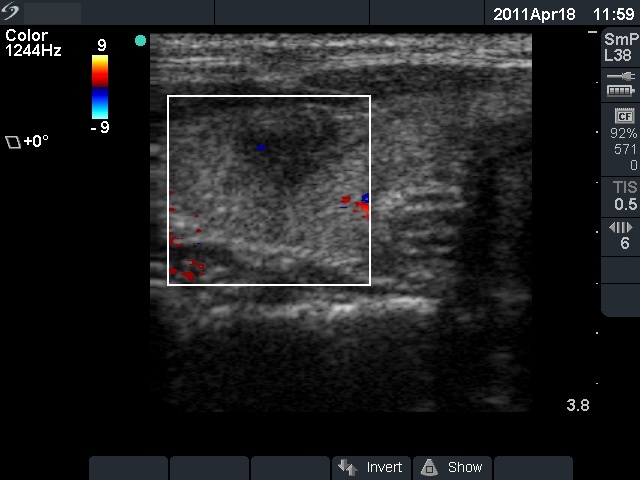

Subacute granulomatous thyroiditis - case 855

Follow-up - 5 months after initial investigation (ultrasonographic picture 5)

Left lobe, longitudinal scan, color Doppler mode. Practially, there is no vascularization on Doppler mode.